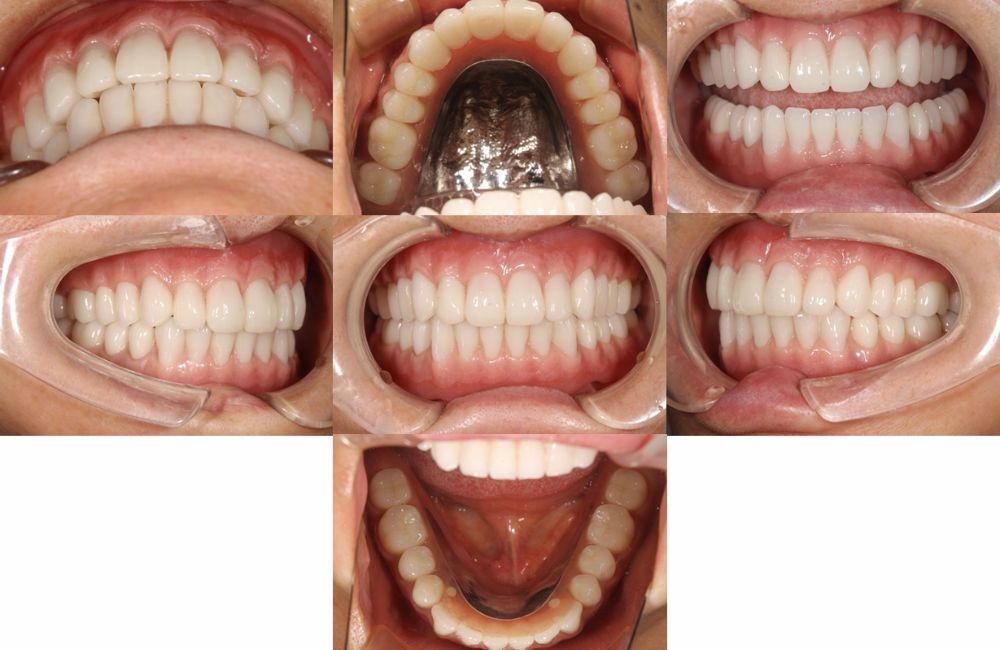

治療前と治療後の口腔内写真と顔貌変化

インプラントオーバーデンチャーの装着前と装着後